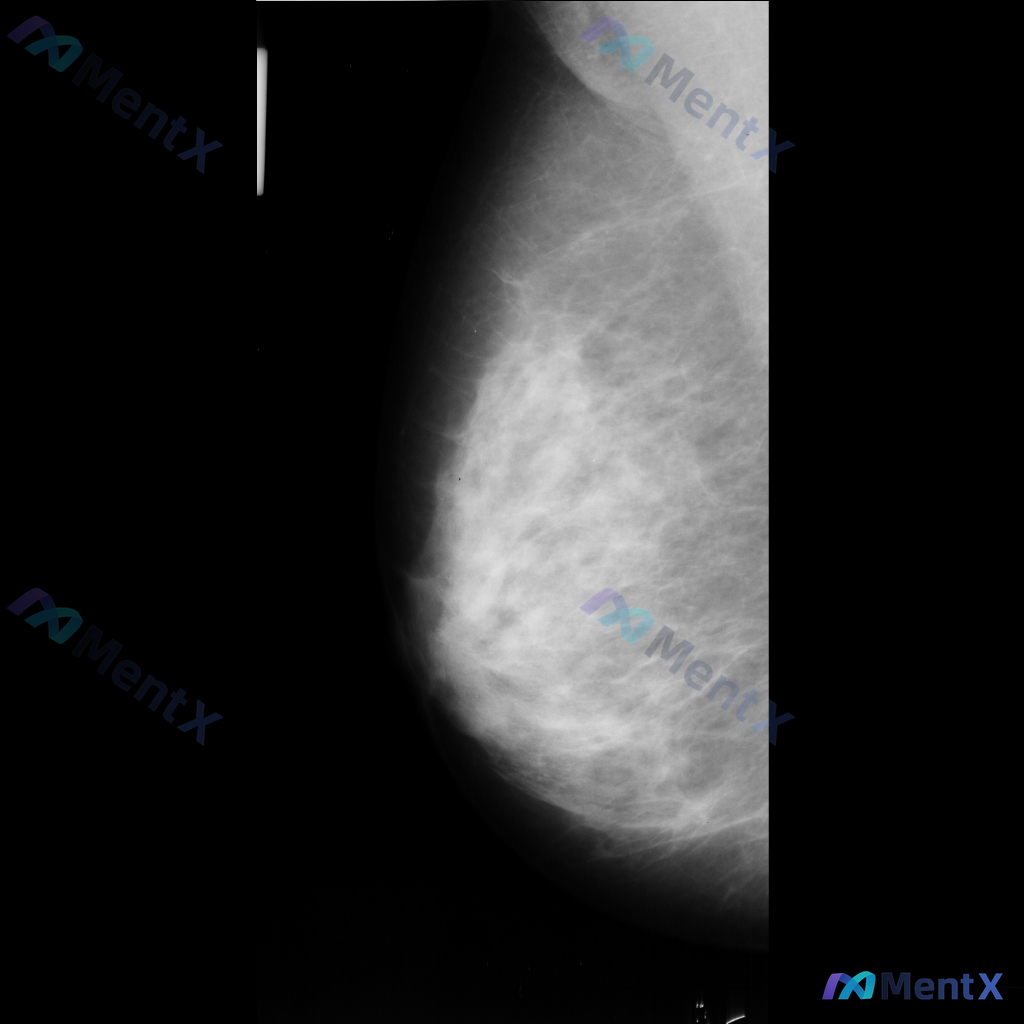

整理到一份乳腺钼靶影像资料,主要异常表现如下: - 部位:乳腺中部偏下方 - 影像征象:局灶性不规则腺体密度增高,伴结构扭曲 - 背景:致密型乳腺 目前仅单张影像资料,未提供其他体位、超声或临床病史。 想和大家讨论一下:单看这组异常表现,你会先往哪个方向考虑?后续如果要进一步明确,你觉得优先做什么检...

整理到一张单侧乳腺钼靶影像的相关描述,分享给大家讨论: - 乳腺背景:腺体组织呈不均匀致密型,脂肪与腺体交错分布 - 主要异常:影像中央偏下方可见一区域性致密影,边界模糊,与周围腺体融合,性质待查 - 其他征象:提及可见散在的、数量极少的细小点状钙化,但无法详细描述形态和分布 目前只有这一张单侧片的...